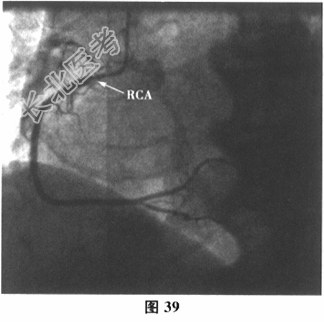

- 多项选择题6.[提示]运动负荷心电图试验示:最大运动功量3.3METs, Ⅱ、Ⅲ、aVF、V3~V4导联ST段压低0.05~0.1mV(图38)。查血小板聚集率:Ara14.57%, ADP36.55%。再次行冠状动脉造影:回旋支近端次全闭塞, LCX内支架内膜重度增生;LAD中段斑块浸润, 最重狭窄30%~40%,轻度肌桥压迫, 第二对角支狭窄70%;RCA近段斑块浸润, 如图39~图41所示。故于回旋支再次植入一枚支架(Promus Element2.75mm×38mm),如图42所示。